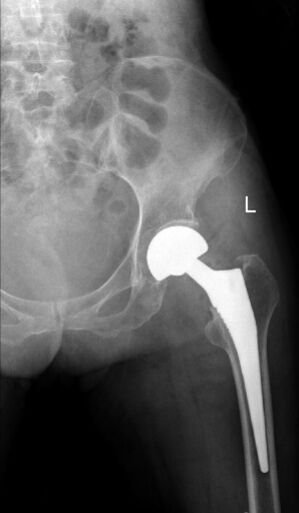

术前x线检查。

就诊,检查后诊断为:左侧股骨颈骨折(头下型),右侧人工股骨头置换术后。原来,老人10年前因摔跤导致右侧股骨颈骨折,在捷克论坛